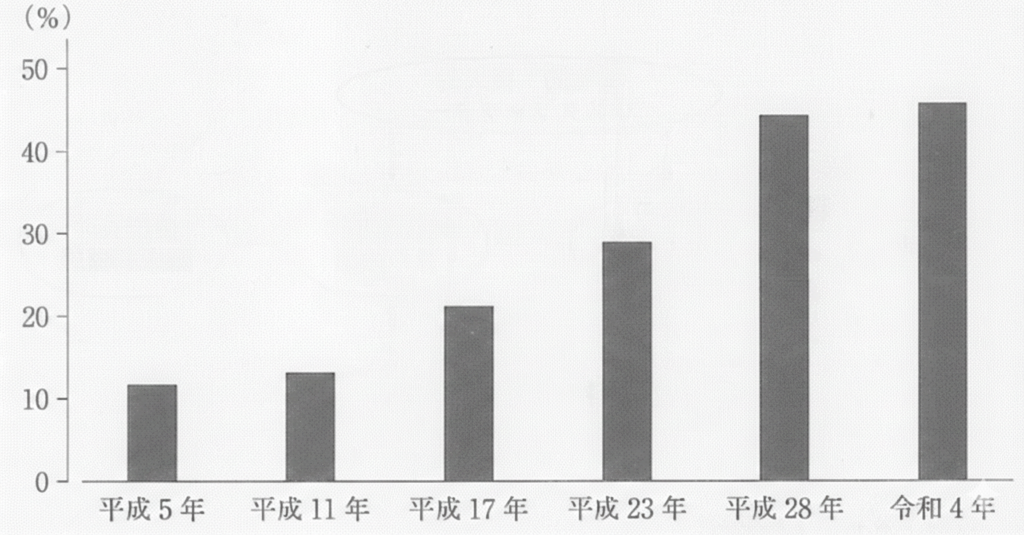

歯科疾患実態調査のある項目の結果を図に示す。この図が示すのはどれか。1つ選べ。

a.20~24歳でう歯をもつ者

b.80~84歳で歯を20本以上有する者

c. l~14歳でフッ化物歯面塗布をしたことのある者

d.40~44歳で4mm以上の歯周ポケットを有する者

解答を見る